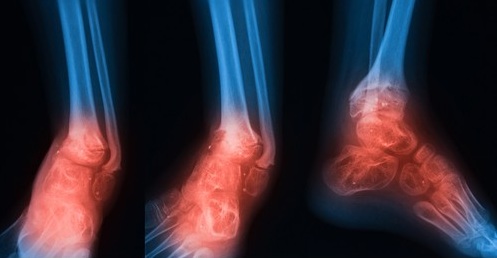

HBOT Treatment Osteomyelitis

Osteomyelitis is an infection of the bone, a rare but serious condition. In most cases, a bacteria called Staphylococcus aureus, a type of staph bacteria, causes osteomyelitis. Infections can reach a bone by traveling through the bloodstream or spreading from nearby tissue. Infections can also begin in the bone itself if an injury exposes the bone to germs. Bones can become infected in a number of ways: Infection in one part of the body may spread through the bloodstream into the bone, an injury, or an open fracture may expose the bone to infection. Certain chronic conditions like diabetes may increase your risk for osteomyelitis. Acute osteomyelitis develops rapidly over a period of seven to 10 days.

HBOT can help to heal bone disorders by stimulating both the osteoclasts and the osteoblasts. This helps and leads to the reabsorption of dead bone and the creation of new bone. In addition, HBOT stimulates the production of new blood vessels, so that the growing bone receives a steady supply of nutrients, including oxygen. This blood vessel network does two other things: it helps support the function of the osteoclasts, and brings infection fighting white blood cells to the area. Osteomyelitis is a bacterial infection that usually involves both the outer layers of the bone and the inner bone marrow. Staphylococci, is a common form of bacteria that can cause infections ranging from pimples to meningitis. Chronic osteomyelitis may follow an acute form or may develop over time; this is also when the acute form is not completely cured by treatment. Long term Osteomyelitis which in some cases continues for years. Refractory osteomyelitis is a term referring to the condition of bone infection that did not respond to either surgical or antibiotic therapy. Part of the difficultly in treating osteomyelitis lies in the fact that it causes a lack of oxygen in the tissues. HBOT, by providing forced oxygenation, helps fight this disorder along with antibiotic therapy and or surgical intervention. Hyperbaric Oxygen Therapy helps preserve healthy bone, restore, and help build new bone and helps with the immune system. In some cases, in both bones and wounds, HBOT draws a clear line by which the surgeon can aid in the removal of dead or diseased bones. These types of infections can occur sometimes in the extraction of a tooth.